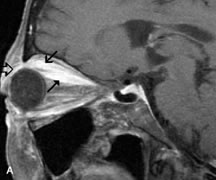

On MRI, uveal melanomas have a typical appearance that helps to differentiate them from other primary and secondary intraocular tumors as well as choroidal detachments. Pigmented melanomas are hyperintense on Tl-weighted images, hypointense on T2-weighted studies, and hyperintense on proton density–weighted examinations (Fig. 24).30,31,50,80–82 These signal characteristics have been attributed to the paramagnetic properties of melanin because of stable free radicals that shorten the T1 and T2 relaxation times. Moderate enhancement is seen on postgadolinium T2-weighted images. Gadolinium-enhanced T1-weighted images are particularly sensitive in detecting choroidal melanomas.83 MRI may be less sensitive in detecting extrascleral extension of tumor than echography performed by an experienced ultrasonographer.84

Fig. 24. A. T1- and (B) T2-weighted MR scans demonstrate a small nodular intraocular mass (arrows) that is very hyperintense on the T1-weighted scan and hypointense on the T2-weighted image. This signal intensity pattern is due to the presence of free radicals within melanin granules. C and D. Postcontrast fat-suppressed T1-weighted scans demonstrate homogeneous intense enhancement of the lesion and no evidence of seleral penetration or optic nerve invasion.